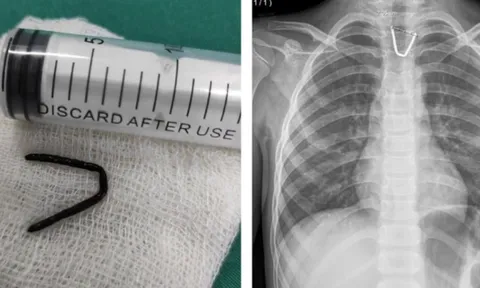

Hoảng hồn khi thấy đoạn kim khí sắc nhọn mắc trong họng bé 8 tuổi

Mới đây, Trung tâm Y tế huyện Tân Sơn (Phú Thọ) vừa thực hiện thành công ca can thiệp lấy dị vật thực quản là đoạn kim khí hình chữ U ra khỏi thực quản bé gái 8 tuổi.